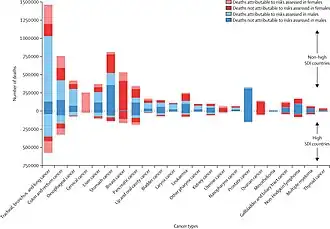

In 2019, ~44% of all cancer deaths – or ~4.5 M deaths or ~105 million lost disability-adjusted life years – were due to known clearly preventable risk factors, led by smoking, alcohol use and high BMI, according to a GBD systematic analysis.[131]

Epidemiology

Estimates are that in 2018, 18.1 million new cases of cancer and 9.6 million deaths occur globally.[213] About 20% of males and 17% of females will get cancer at some point in time while 13% of males and 9% of females will die from it.[213]

In 2008, approximately 12.7 million cancers were diagnosed (excluding non-melanoma skin cancers and other non-invasive cancers)[26] and in 2010 nearly 7.98 million people died.[214] Cancers account for almost one in six deaths. The cancers causing the most deaths, as of 2020 are lung cancer (1.8 million), colorectal cancer (916,000), liver cancer (830,000), stomach cancer (769,000) and breast cancer (685,000).[2] This makes invasive cancer the leading cause of death in the developed world and the second leading in the developing world.[26] Over half of these cases occur in the developing world.[26]